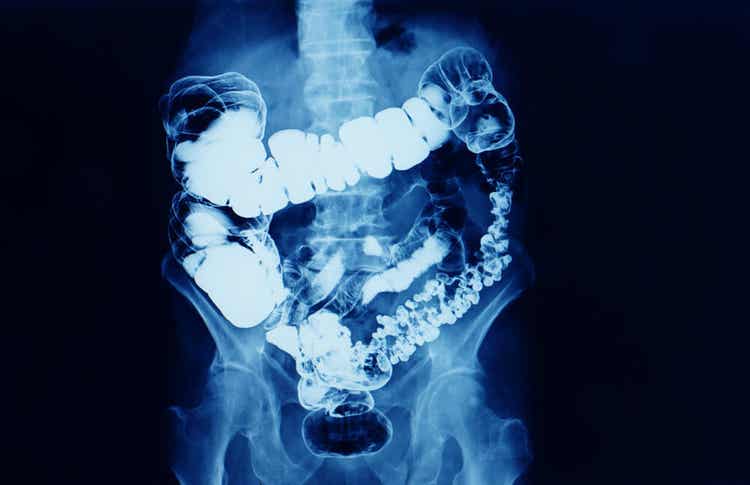

La Journée mondiale du cancer du côlon fait référence à la maladie cancéreuse qui se développe dans le gros intestin et le rectum. Le terme de cancer colorectal est également une façon de désigner cette localisation.

Le gros intestin et le rectum sont la dernière partie du tube digestif après l’intestin grêle. C’est là que se forment les matières fécales qui seront expulsées du corps en transportant des déchets. Le bol alimentaire est déshydraté dans le gros intestin et stocké dans le rectum pour être expulsé.